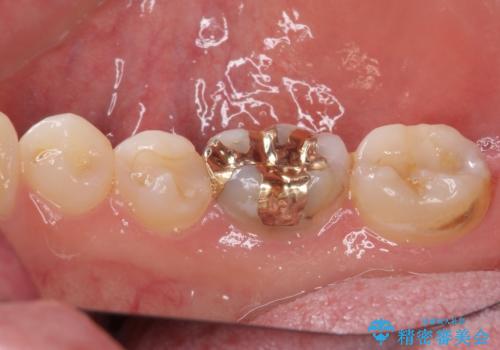

仮詰め材を外すと虫歯が残っていたので、全てを取り除いた後に、ゴールドインレーの型どりを行いました。

ゴールドインレーをご自身で選択いただいたものの、どういった仕上がりとなるか不安を感じていたようですが、実際に装着された口腔内をご覧になり、思ったほど金属色が気にならないとのことでした。